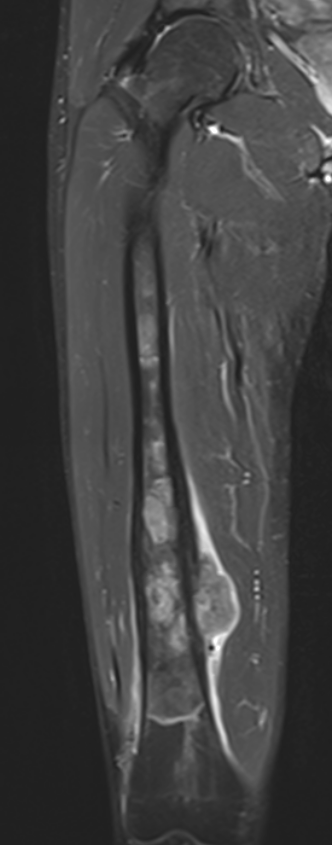

MRI

Evaluate

i) Soft tissue component

ii) Involvement of neurovascular bundle

iii) Marrow extent of tumour

- helpful in determining appropriate resection level

- satellite lesions - metastasis within reactive zone

iv) Identify skip lesions

- metastasis outside reactive zone

- sagittal and coronal images of the entire bone

v) Joint involvement